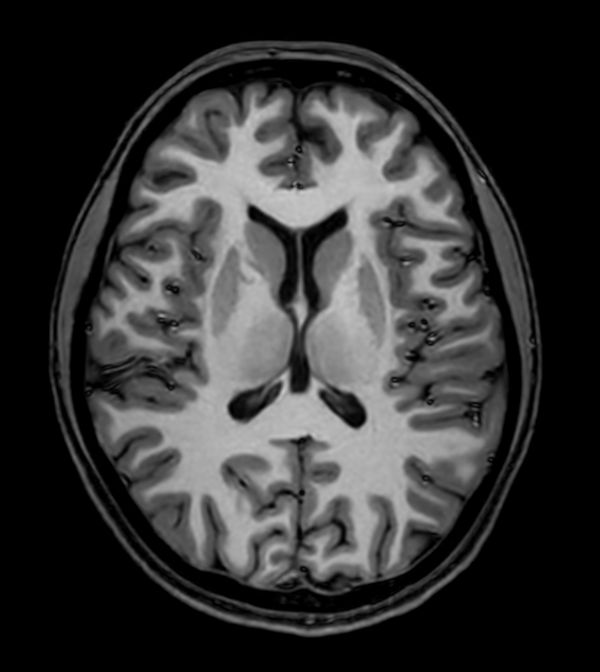

Sagittal 3D T1w TFE

-

3D T1w TFE (Axial reformat)

3D T1w TFE (Coronal reformat)